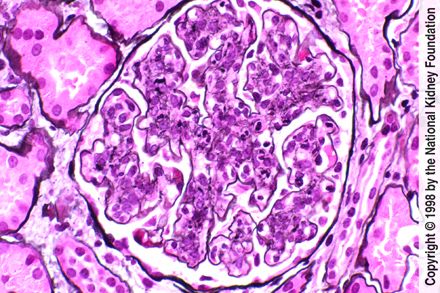

Welcome to our eighth event of the semester! We will be teaching you about all things to do with Glomerulonephritis on Wednesday the 16th of March at 7:00pm. We will be running through the basics you need to know for TCD and some tips for Progress Test and OSCEs!